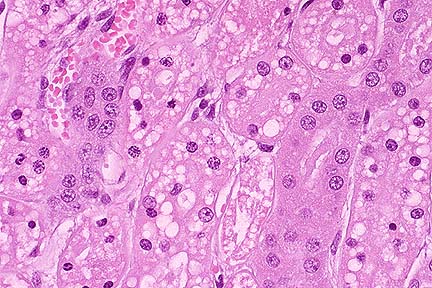

Suppurative and necrotizing myocarditis with colonies of extracellular H. somnus bacilli in a feedlot calf. (HE, 400X, 67K)

Contributor's Diagnosis and Comments: Myocarditis, purulent and necrotizing with septic infarction, acute, severe. Etiology: Hemophilus somnus. There were also lesions in the brain compatible with H. somnus-induced Thromboembolic meningoencephalitis (T.E.M.E.).

AFIP Diagnosis: Heart: Myocarditis, necrosuppurative, multifocal, moderate, with necrotizing vasculitis, fibrin thrombi, and intravascular and extravascular bacilli, cross breed, bovine.

Conference Note: Hemophilus somnus is a small gram-negative, pleomorphic coccobacillus that is a commensal organism of the bovine urogenital and respiratory tracts. In cattle, H. somnus causes a septicemia that predominantly affects immature cattle, causing acute death or localization in one or several organs. Affected cattle have usually been subjected to increased environmental stress, including weaning and shipping. The route of transmission and mechanism by which H. somnus invades the bloodstream are unknown; the organism is able to survive phagocytosis and readily replicate within bovine macrophages. Upon entering the vascular system, the bacteria adhere to endothelial cells causing them to contract and expose the subendothelial collagen. The exposed collagen initiates the intrinsic coagulation cascade, causing thrombosis. The presence of the bacteria also induces an inflammatory response that results in vasculitis. Vasculitis and thrombosis can develop in any organ but cerebral vessels are especially vulnerable; vasculitis and thrombosis of these vessels results in thrombotic meningoencephalitis, the most characteristic lesion of H. somnus infection.

In North America, localization of H. somnus in myocardium is common and results in vasculitis and myocardial infarction or myocardial abscessation. Myocardial abscesses are most common in the left ventricular free wall, particularly the papillary muscles. Death in these animals is usually caused by cardiac failure.